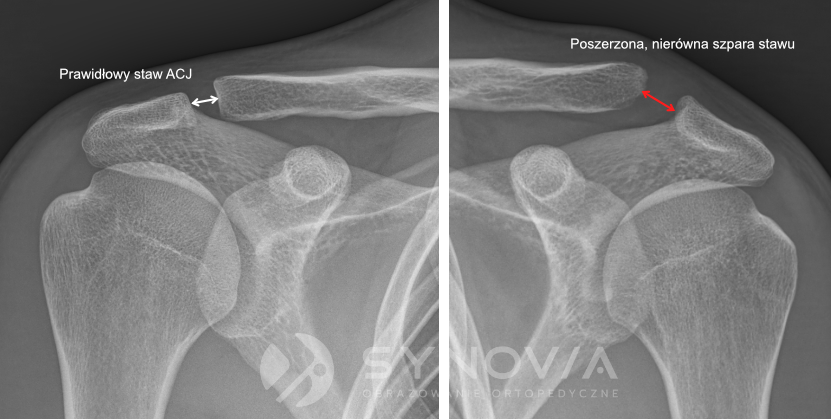

Urazy barku – zwichnięcie / skręcenie /staw barkowo – obojczykowy (ACJ) – 2–4%

Zwykle wynikają z upadku na bok. W przypadku zwichnięcia można podejrzewać współistniejące uszkodzenia obrąbka lub złamania typu Hill-Sachsa.